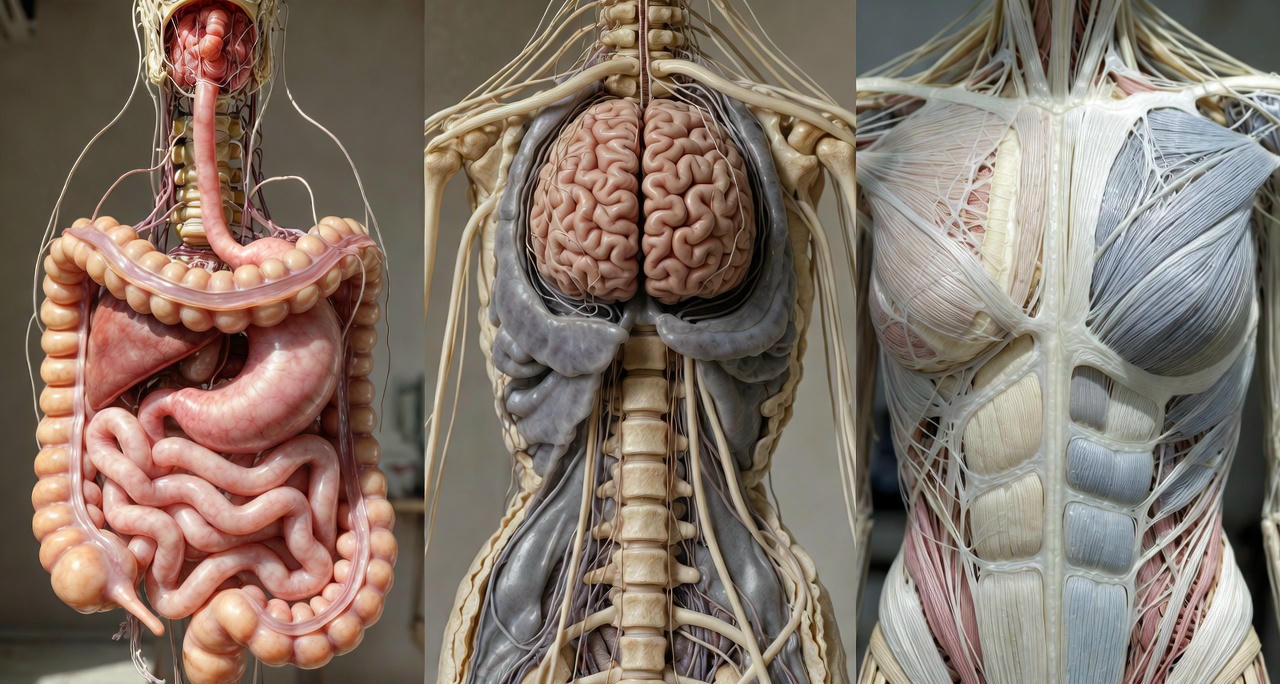

Fascia is your body's living, continuous web of connective tissue. It wraps every single muscle fibre, every nerve, every bone, every organ, forming one uninterrupted three-dimensional network from head to toe. It's richly supplied with nerves and plays an active role in how your body feels and moves.

Your nervous system is designed with two opposing modes. Fight-or-flight, the sympathetic branch, prepares you for action: heart racing, muscles tensing, senses sharpening to face a threat.

The opposite mode, rest-digest-heal, driven by the parasympathetic branch, allows recovery: slowing the heart, relaxing tissues, repairing damage.

Your gut houses trillions of bacteria that aren't just digesting food. They produce chemicals that travel throughout your body, influencing inflammation, nervous system balance, and even pain processing.